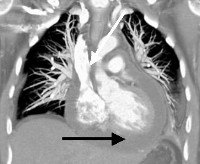

ЭКГ в случае экссудативного перикардита выявляет снижение амплитуды всех зубцов. Мультиспиральная КТ подтверждает наличие патологического выпота и утолщение перикардиальных листков. Для уточнения причины экссудации и верификации диагноза экссудативного перикардита выполняют пункцию перикарда и исследование характера перикардиальной жидкости (общеклиническое, бактериологическое, цитологическое, анализ на AHAT и LE-клетки). Возможно проведение биопсии перикарда с морфологическим исследованием полученной ткани.